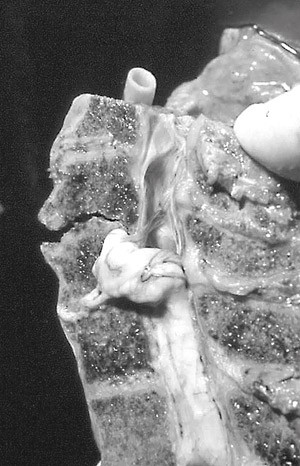

Det er nærmest horisontale leddflater mellom C1 og C2, i motsetning til hos menneskeapene, hvor de skrår ca. 45° nedover i lateral retning slik at C1 blir liggende som en stabil «ring» utenpå C2 (1). I begge tilfeller tillater atlantoaksialleddet rotasjon, og kalles derfor «nei-leddet». Leddkapselen er tynn og vid, og med kraftige synoviale folder som noen ganger kan legge seg inn i leddspalten (5). Vekten av hodet (pluss halsmuskulaturens tonus/kontraksjonskraft) fordeles på atlantooksipitalleddene, overføres til de to atlantoaksialleddene, og derfra til mellomvirvelskiven C2–C3. Axis blir derfor et element i halsvirvelsøylen hvor de laterale kreftene sentraliseres (fig 1).

Mens virvellegemene er bærende, er de skråttstilte fasettleddene styrende for bevegeligheten mellom virvlene. De motstår sagittale krefter bakfra (mens det ved tilsvarende krefter forfra kun er ligamentene som holder igjen), med unntak av dens axis, som stikker opp bak fremre bue på C1. Dens danner et synovialt ledd mot C1 i en grop (fovea dentis) på innsiden av buen. Den bakre flaten artikulerer med et tversgående ligament (ligamentum transversum atlantis) som danner et ekte ledd, idet ligamentet har en hinne av fiberbrusk som artikulasjonsflate. Den sidestøtten som processus uncinatus representerer, gjelder ikke for C1, som kun har en viss sidestøtte i fovea dentis ved hjelp av ligamentene omkring. Det gjør atlantoaksialleddet særlig sårbart ved krefter som virker sideveis og bakfra, mens de øvrige delene av cervikalcolumna i mindre grad tåler krefter som virker forfra.

I cervikalcolumna er mellomvirvelskivene formet annerledes enn i resten av ryggsøylen. De er spaltet på sidene, omtrent som en todelt lagkake. Spaltene finnes ikke hos småbarn, men dannes først fra åtte-ti-årsalderen og synes å utvikle og forandre seg gjennom hele livet. Spalten kan gå gjennom hele skiven, hvilket medfører at nucleus pulposus forholdsvis lett kan presses ut og fordeles over et større område enn i de øvrige virvelavsnitt (fig 3).

Spaltene bidrar til nakkens bevegelighet, men siden de dukker først opp omkring C3–C5-nivået, hvor vi finner den sterkeste lordosen og belastningen i halsen (5), har det vært antydet at de er uttrykk for sprekkdanning på grunn av belastning (5, 17). Imidlertid finnes de hos alle mennesker, og fiberretningen viser at hvert av de to lagene danner en separat, fysiologisk enhet (fig 4). Etter hvert dannes det bindevev på sidene, lik en leddkapsel som lukker spaltene lateralt.